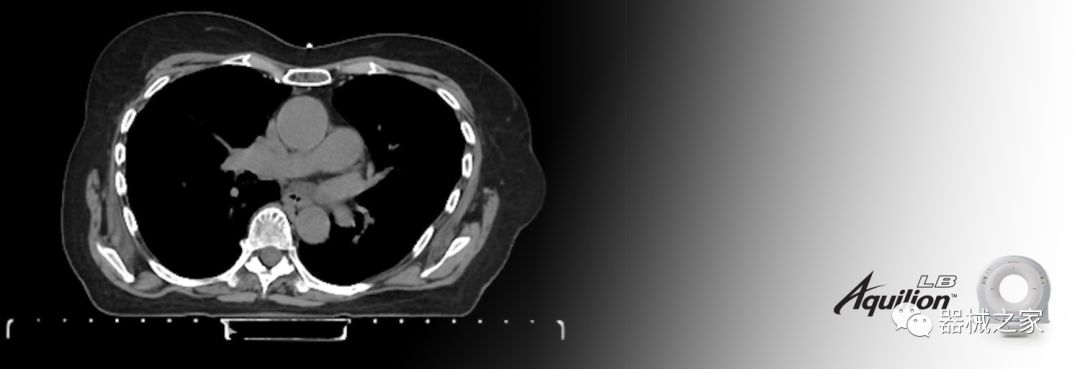

在以患者為中心的放射腫瘤學領域,計算機斷層掃描(CT)的可訪問性,可重復性和靈活性至關重要。為了建立這些價值,佳能醫(yī)療系統(tǒng)美國公司現(xiàn)在正在擴大其放射腫瘤學CT模擬產(chǎn)品,包括Aquilion Prime SP和Aquilion Lightning 80高級CT系統(tǒng)。除了Aquilion LB之外,Aquilion Prime SP和Aquilion Lightning 80現(xiàn)在還包括放射治療(RT)選項,可為腫瘤學規(guī)劃提供高質(zhì)量的CT成像和精密工具。

佳能醫(yī)療的Aquilion Lightning 80掃描儀還以緊湊,經(jīng)濟的包裝提供高質(zhì)量的成像。Aquilion Lightning 80旨在可靠,高效地運行,在繁忙的環(huán)境中生成高質(zhì)量的圖像。

Aquilion LB專為滿足腫瘤學挑戰(zhàn)而設計,同時優(yōu)先考慮患者護理。Aquilion LB的內(nèi)徑為90 cm,能夠幫助復雜的患者設置并提高患者的舒適度。CT模擬定位可以輕松鏡像放射治療定位,更加自信。該系統(tǒng)采用0.5 mm x 16排(32層)PUREViSION探測器技術,70 cm視野,AIDR 3D和SEMAR技術。